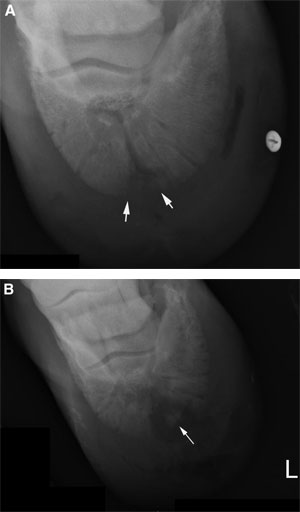

Клинический осмотр схож с осмотром других колотых ран и очень часто с его помощью находится дренажный путь, ведущий к копытной кости. Порой, лошадь, системно находящаяся на антибиотиках и противовоспалительных препаратах, не покажет заметной хромоты или вытекания жидкости пока не прекратится применение лекарств/антибиотиков. Как бы там ни было, рентген должен показать поврежденную зону, чтобы определить наличие остеита или омертвления костных тканей. (рис.2)

Рис.2: (А): Септическое воспаление копытной кости на рентгене. (Б): Септическое воспаление копытной кости с начавшимся процессом омертвления костной ткани.